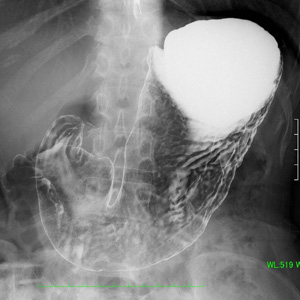

Q2) どうして胃や大腸の検査の時、回転したり体を動かしたりするのですか?

|

![]() |

A2) 胃や腸の壁の内側にバリウムを付着させて観察する検査なのでムラなく壁全体にバリウムを着けるためです。 |